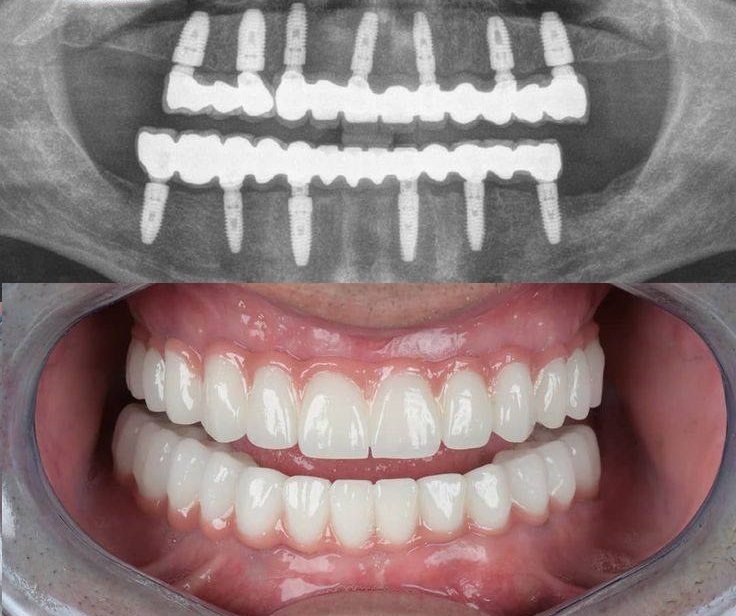

ایمپلنت کامل دهان، که با عنوان «ایمپلنت کامل فک بالا و پایین» نیز شناخته می شود، یکی از کارآمدترین روش های بازسازی کامل دهان برای بیمارانی است که تمام یا بخش عمده ای از دندان های خود را از دست داده اند. در این روش، مجموعه ای از پروتزهای ثابت بر پایهٔ چند فیکسچر در استخوان فک انسان قرار می گیرند و جایگزینی پایدار و بادوام برای دندان های طبیعی فراهم می کنند. یکی از رایج ترین رویکردها در این زمینه، تکنیک All-on-6 است که با استفاده از شش فیکسچر استراتژیک، امکان حمایت کامل یک قوس دندانی را فراهم می کند و عملکرد جویدن و زیبایی لبخند بیمار را به شکل مؤثری باز می گرداند.

در ایمپلنت کامل فک، فیکسچرهای تیتانیومی به عنوان ریشه های مصنوعی در استخوان فک قرار می گیرند. پس از مرحله اُستئواینتگریشن، یعنی جوش خوردن ایمپلنت با استخوان، پروتز ثابت دندانی روی آنها نصب می شود تا عملکردی مشابه دندان طبیعی در جویدن، تکلم و زیبایی ایجاد شود.

استفاده از تکنیک All-on-6 در این روش باعث می شود شش پایه استراتژیک به طور بهینه در فک قرار گیرند، پایداری پروتز افزایش یابد و نیروهای جویدن به صورت یکنواخت توزیع شود.

تکنیک All-on-6 یکی از روش های پیشرفته بازسازی کامل فک است که در آن شش فیکسچر تیتانیومی یا آلیاژهای مقاوم مانند روکسولید در نواحی دارای بیشترین تراکم استخوانی قرار داده می شود. جایگذاری دقیق و استراتژیک این فیکسچرها امکان ایجاد تکیه گاهی پایدار برای یک پروتز ثابت کامل را فراهم می کند و موجب می شود نیروهای جویدن به طور یکنواخت در فک توزیع شود.

به دلیل تعداد بیشتر پایه ها، این روش نسبت به تکنیک All-on-4 پایداری بالاتری دارد و برای بیمارانی که از نظر کیفیت و حجم استخوان وضعیت نسبتاً مناسبی دارند، گزینه ای مطمئن تر محسوب می شود. استفاده از شش ایمپلنت، ثبات پروتز را افزایش داده و شرایطی فراهم می کند که بیمار بتواند با آسودگی غذا بخورد، صحبت کند و عملکرد دهانی طبیعی تری را تجربه کند.

نصب پروتز موقت و سپس پروتز نهایی

پس از اتمام مرحله جوش خوردن ایمپلنت ها، پروتز موقت یا نهایی روی فیکسچرها قرار می گیرد. پروتزهای ثابت متصل به ایمپلنت امکان جویدن و صحبت کردن طبیعی را فراهم می کنند و ظاهر کاملاً طبیعی دارند.